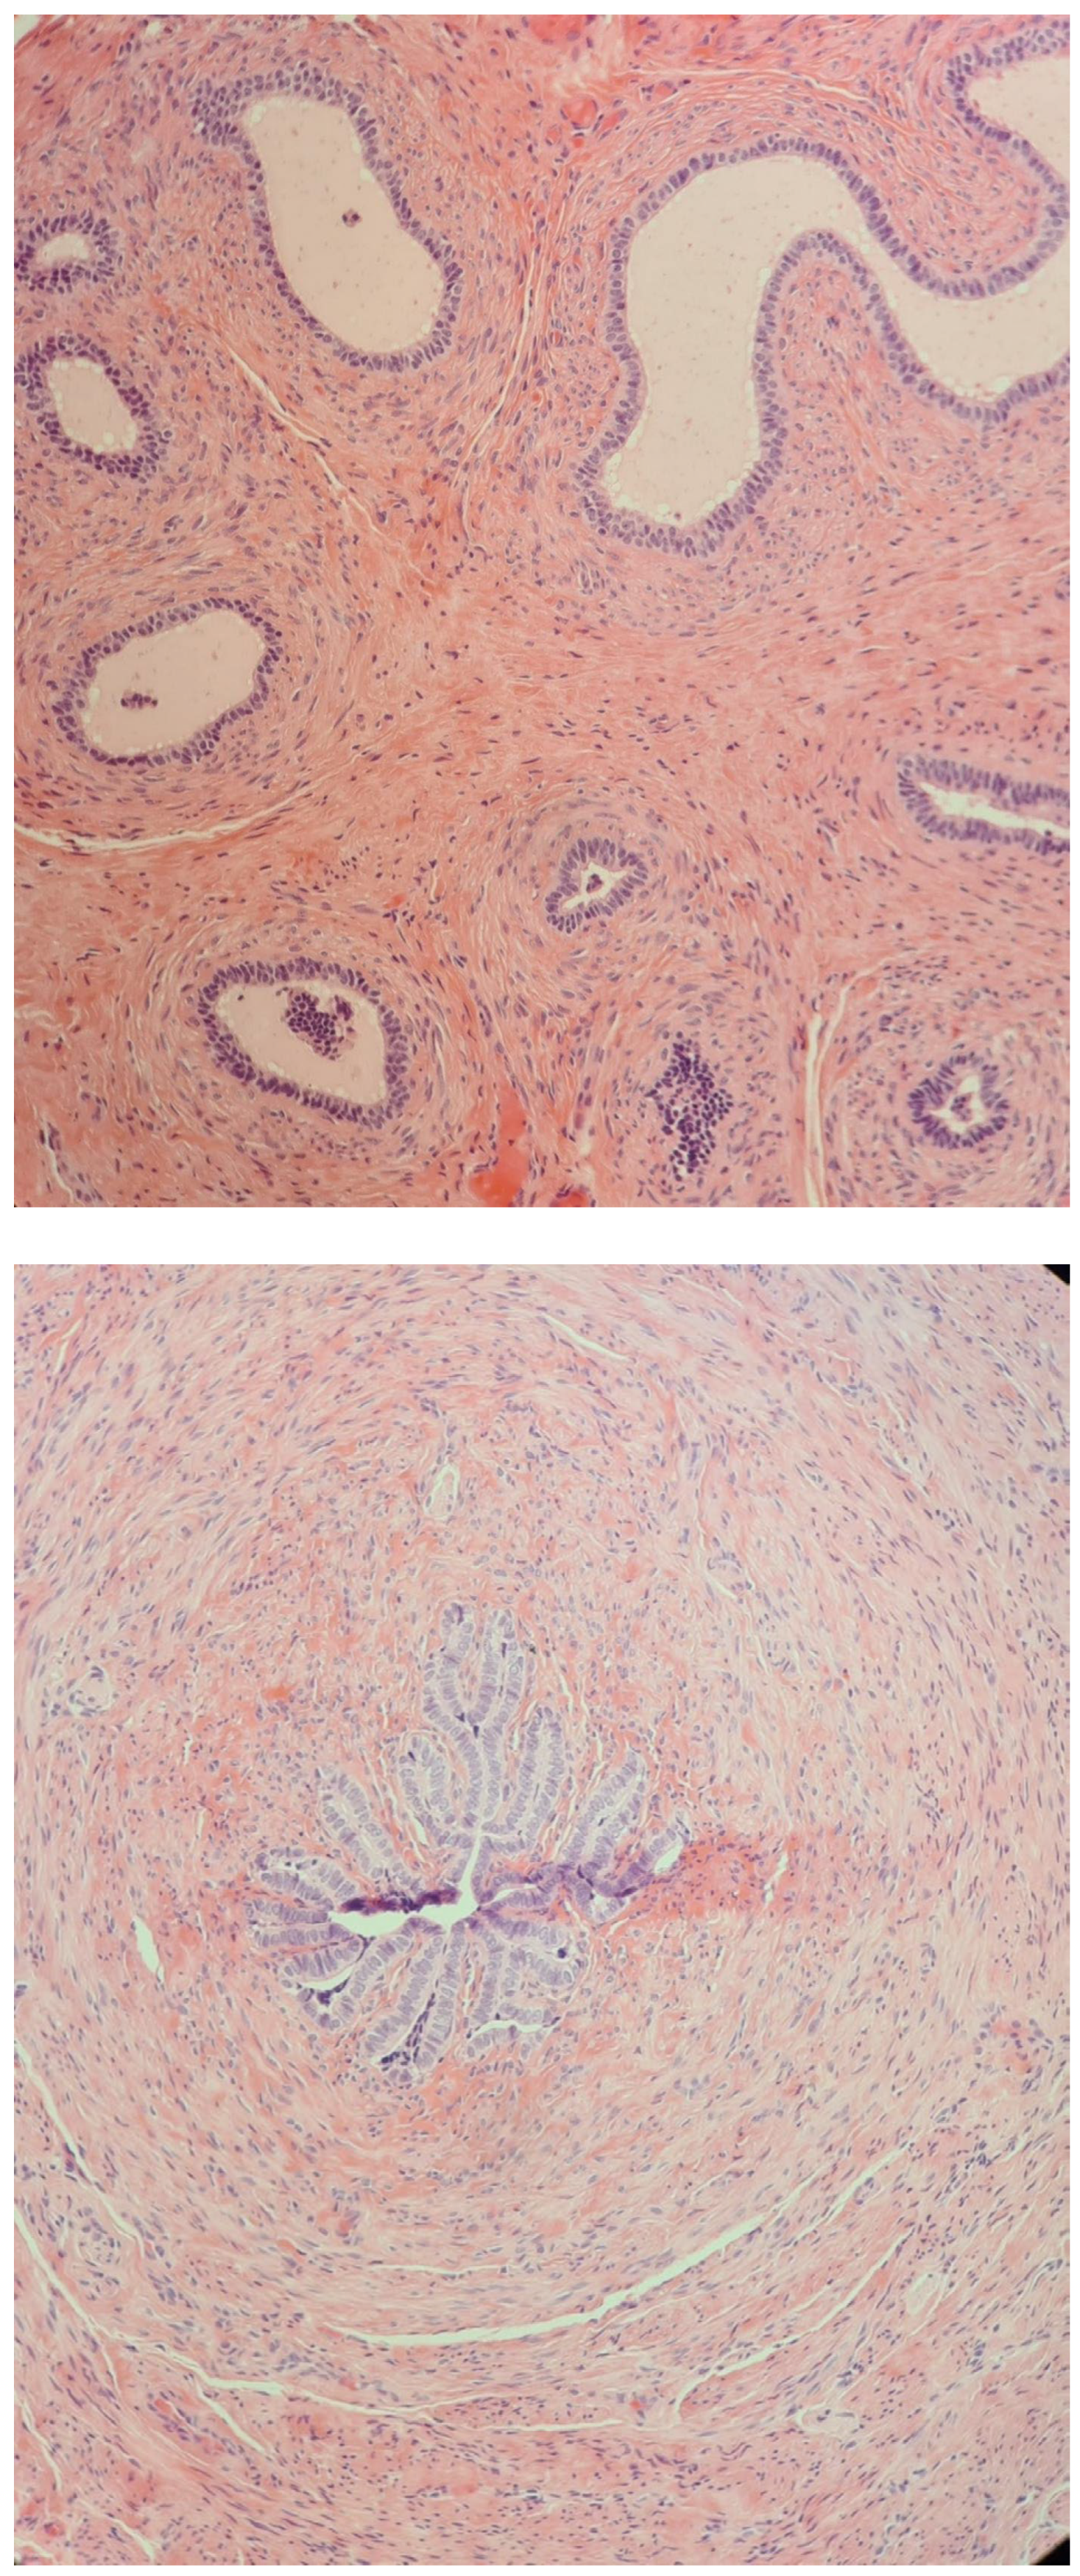

2.4. At Age 13 Years